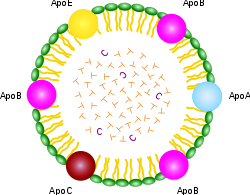

Τα λίπη χωνεύονται στο έντερο και απελευθερώνονται στην κυκλοφορία του αίματος με τη μορφή μιας σχετικά μεγάλης σφαίρας με ένα προστατευτικό στρώμα πρωτεΐνης, που ονομάζεται χυλομικρό. Το χυλομικρό μπορεί να παρέχει άμεσα καύσιμο σε πολλούς τύπους κυττάρων, αλλά μπορεί επίσης να σταλεί στο ήπαρ, όπου τα λίπη που περιέχονται σαυτό διευθετούνται και αναδιανέμονται σε πολύ μικρότερα σωματίδια, τα οποία περιέχουν επίσης σημαντικές ποσότητες χοληστερόλης. Αυτά τα σωματίδια που ονομάζονται “λιποπρωτεΐνες,” (εφεξής, LPP LiPoProteins) επειδή περιέχουν πρωτεΐνη στην επιφάνεια της σφαίρας και λιπίδια (λίπη) στο εσωτερικό. Αν εχετε μετρήσει τη χοληστερόλη σας, πιθανώς θα έχετε ακούσει για την LDL (χαμηλής πυκνότητας LPP) “κακή” και την HDL (υψηλής πυκνότητας LPP) “καλή”. Αν νομίζετε ότι πρόκειται για δύο διαφορετικά είδη της χοληστερόλης, κάνετε λάθος. Είναι μόνο δύο διαφορετικά είδη δοχείων για τη χοληστερόλη και τα λιπαρά που εξυπηρετούν διαφορετικούς ρόλους στο σώμα. Υπάρχουν πράγματι αρκετές άλλες λιποπρωτεϊνες (LPP), για παράδειγμα, η VLDL (πολύ-χαμηλή) και IDL (ενδιάμεση), όπως φαίνεται στο συνοδευτικό διάγραμμα. Σε αυτό το δοκίμιο θα αναφερθώ σε αυτά, συλλογικά ως XDL.( χ-πυκνότητας λιποπρωτεϊνες όπου χ= χαμηλή – υψηλή κλπ).

Τα λίπη χωνεύονται στο έντερο και απελευθερώνονται στην κυκλοφορία του αίματος με τη μορφή μιας σχετικά μεγάλης σφαίρας με ένα προστατευτικό στρώμα πρωτεΐνης, που ονομάζεται χυλομικρό. Το χυλομικρό μπορεί να παρέχει άμεσα καύσιμο σε πολλούς τύπους κυττάρων, αλλά μπορεί επίσης να σταλεί στο ήπαρ, όπου τα λίπη που περιέχονται σαυτό διευθετούνται και αναδιανέμονται σε πολύ μικρότερα σωματίδια, τα οποία περιέχουν επίσης σημαντικές ποσότητες χοληστερόλης. Αυτά τα σωματίδια που ονομάζονται “λιποπρωτεΐνες,” (εφεξής, LPP LiPoProteins) επειδή περιέχουν πρωτεΐνη στην επιφάνεια της σφαίρας και λιπίδια (λίπη) στο εσωτερικό. Αν εχετε μετρήσει τη χοληστερόλη σας, πιθανώς θα έχετε ακούσει για την LDL (χαμηλής πυκνότητας LPP) “κακή” και την HDL (υψηλής πυκνότητας LPP) “καλή”. Αν νομίζετε ότι πρόκειται για δύο διαφορετικά είδη της χοληστερόλης, κάνετε λάθος. Είναι μόνο δύο διαφορετικά είδη δοχείων για τη χοληστερόλη και τα λιπαρά που εξυπηρετούν διαφορετικούς ρόλους στο σώμα. Υπάρχουν πράγματι αρκετές άλλες λιποπρωτεϊνες (LPP), για παράδειγμα, η VLDL (πολύ-χαμηλή) και IDL (ενδιάμεση), όπως φαίνεται στο συνοδευτικό διάγραμμα. Σε αυτό το δοκίμιο θα αναφερθώ σε αυτά, συλλογικά ως XDL.( χ-πυκνότητας λιποπρωτεϊνες όπου χ= χαμηλή – υψηλή κλπ).

Σαν να μην έφταναν τα παραπάνω, υπάρχει και μία άλλη μοναδική XDL που βρίσκεται μόνο στο εγκεφαλονωτιαίο υγρό, που τροφοδοτεί τον εγκέφαλο και το νευρικό σύστημα. Αυτη δεν φαίνεται να έχει ακόμη όνομα, αλλά θα την ονομάσουμε “B-HDL,« διότι είναι σαν την HDL από την άποψη του μεγέθους του, και “Β” γιατί είναι “του εγκεφάλου (Brain) [13]”

Ένα σημαντικό σημείο για όλα τα XDL είναι ότι περιέχουν σαφώς διαφορετικές συνθέσεις, και η καθε μία είναι προγραμματισμένη για συγκεκριμένους ιστούς. Μια σειρά από πρωτεΐνες που ονομάζονται “απολιποπρωτεϊνες» ή, ισοδύναμα, “apoproteins” (“απο’ς “ για συντομία) αποτελουν το μοτίβο για το ποιός λαμβάνει τι.Όπως μπορείτε να δείτε από το σχηματικό του chylomicron που απεικονίζεται στα δεξιά, περιέχει ένα ουράνιο τόξο

διαφορετικών apo για κάθε πιθανή εφαρμογή.Αλλά τα XDL είναι πολύ πιο εξειδικευμένα, με την HDL να περιέχει “Α”,η LDL περιέχει “Β”,η VLDL περιέχει “Β” και “C”, και η IDL που περιέχει μόνο “Ε.” Οι apo έχουν συγκεκριμένες δεσμευτικές ιδιότητες που επιτρέπουν το περιεχόμενο των λιπιδίων που έχουν να μεταφέρονται μέσω των μεμβρανών των κυττάρων, έτσι ώστε το κύτταρο να αποκτά πρόσβαση στα λιπαρά και τη χοληστερόλη που βρίσκεται μέσα.

Τώρα θέλω να επανέλθω στο θέμα τως XDLς. Το ταξίδι από το ήπαρ προς τον εγκέφαλο, είναι επικίνδυνο καθώς το οξυγόνο και τα βακτήρια βρίσκονται σε αφθονία στο αίμα. Το προστατευτικό κέλυφος των XDL περιέχει τόσο LPP αλλά και μη εστεροποιημένη χοληστερόλη, καθώς και την υπογραφή των αντίστοιχων apoς που ελέγχουν ποιά κυτταρα θα παραλάβουν τα περιεχόμενα όπως φαίνεται στο αντίστοιχο σχήμα. Τα εσωτερικα συστατικά είναι εστεροποιημένη χοληστερόλη και λιπαρά οξέα, καθώς και συγκεκριμένα αντιοξειδωτικά τα οποία μεταφέρονται στα κύτταρα συσκευασμένα στο ίδιο φορτίο.